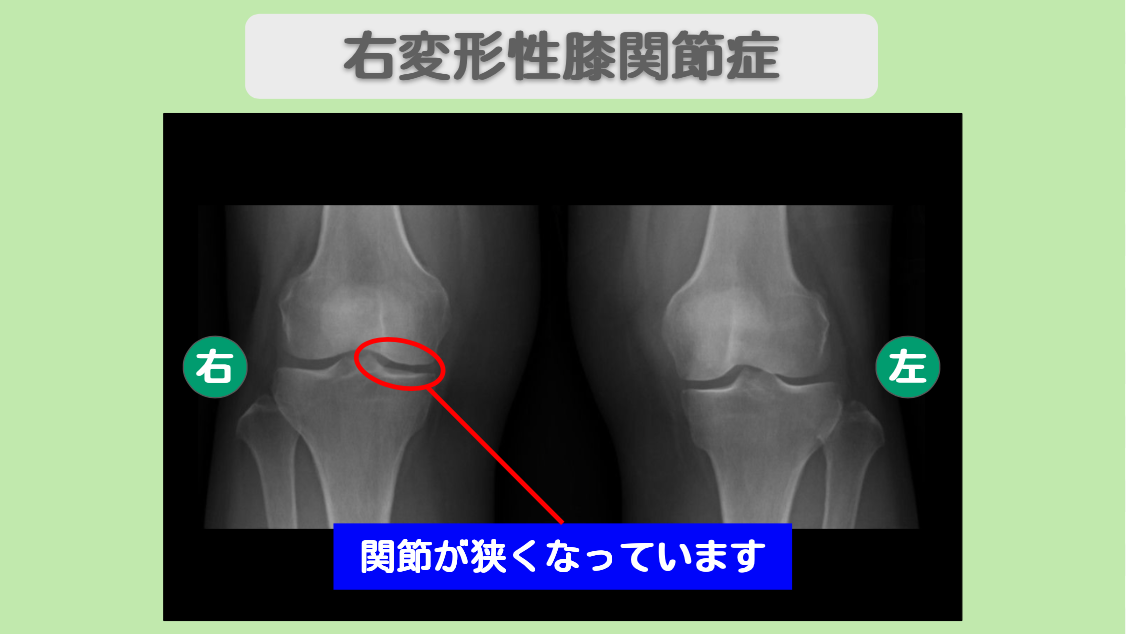

痛み改善で半月板の手術回避! 左半月板損傷・右変形性膝関節症 60代女性

1か月前に整形外科を受診され、MRI撮影で左膝半月板内側後方の水平断裂と両膝の初期の変形性関節症と診断されました。現在は、30分以上立っていることができず、15分ほど歩行すると痛みが強くなり、しゃがみ込むのも難しい状態でした。ヒアルロン酸注射を行っても効果がなく、手術を躊躇されて、当院にいらっしゃいました。

MRI・レントゲン所見

MRIにて半月板の損傷を認めます。